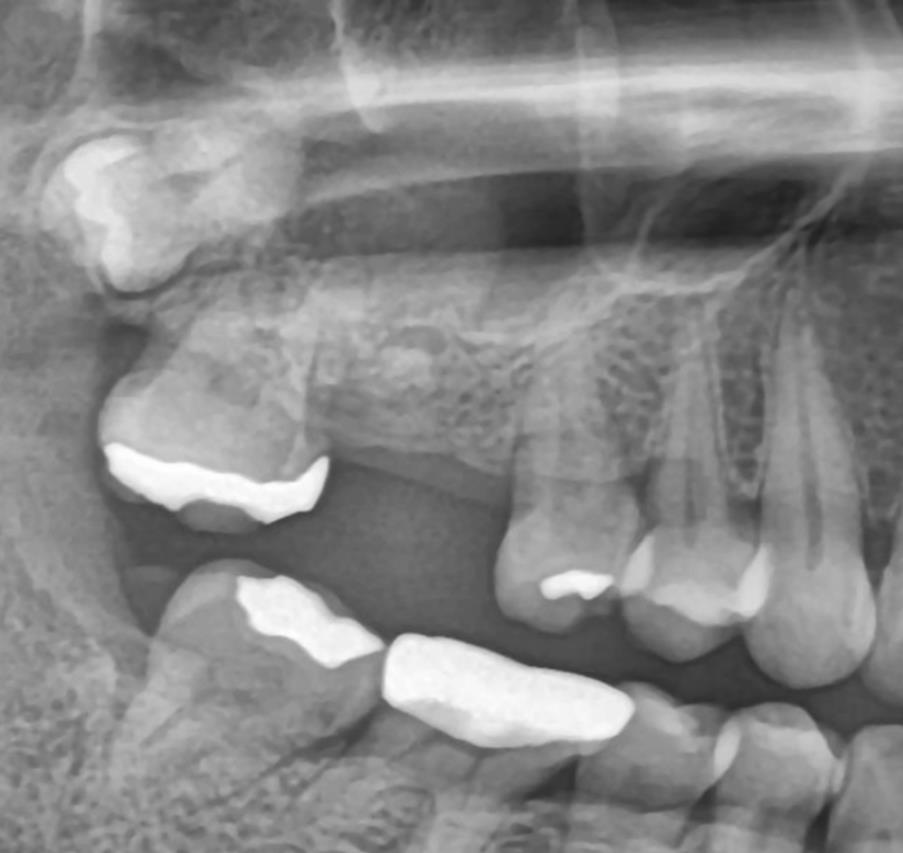

수술 전 파노라마 – 상악동과 인접한 위치 확인

수술 전 CT – 뼈 높이가 부족해 상악동 거상술 필요 소견